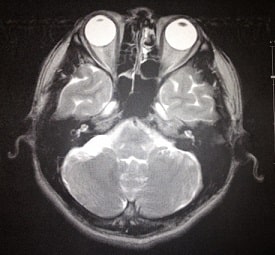

医療機関における脳腫瘍の診断は、頭部X線単純撮影、造影を含めたCT検査、MRI検査、脳血管撮影を行い、腫瘍に特徴的な所見から診断します。